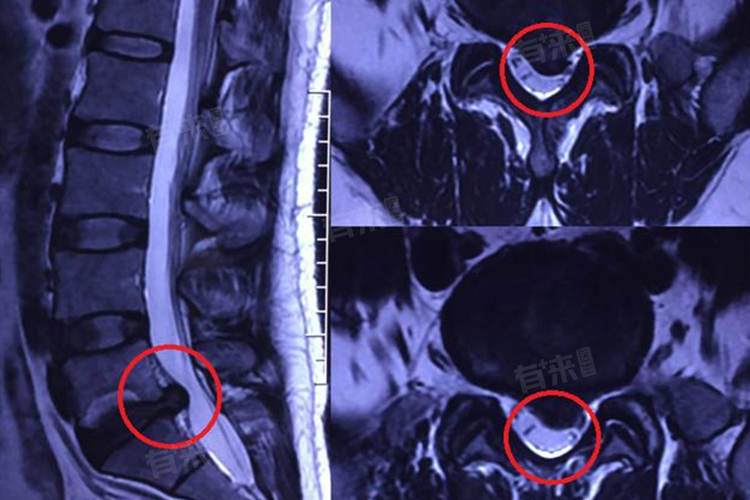

- 当神经受到严重压迫时,如长期的腰椎间盘突出、颈椎管狭窄或肿瘤压迫等,患者可能表现出明显的疼痛、无力、肌肉萎缩甚至神经断裂等症状。此时,恢复时间将大大延长,可能需要6-12个月甚至更长时间。对于这类患者,通常需要采取手术治疗来解除压迫,并在术后进行长期的康复治疗和锻炼。由于神经受损严重,恢复过程可能较为缓慢,且部分患者可能无法完全恢复到正常状态。